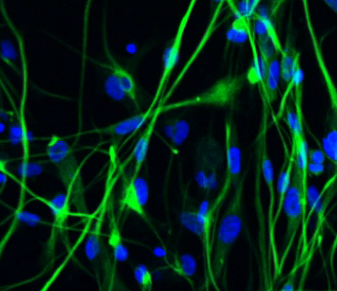

Una nuova ricerca dimostra che il glioma, il più letale dei tumori cerebrali umani, aumenta la sua crescita dirottando alcuni meccanismi della neuroplasticità che normalmente aiutano il cervello a formare nuove sinapsi.

Il team di ricerca ha identificato una proteina specifica, chiamata neuroligin-3, che è in gran parte responsabile dell’aumento della crescita tumorale associata con l’attività neuronale nella corteccia cerebrale. Neuroligin-3 ha avuto effetti simili in tutti i diversi tipi di gliomi ad alto grado, nonostante il fatto che questi tumori hanno caratteristiche molecolari e genetiche differenti. “Vedere un fattore microambientale che influenza tutte queste classi ben distinte di gliomi, è stata una grande sorpresa “, ha detto Monje.

E l’identità del fattore era anche inaspettata. Nel tessuto sano, neuroligin-3 aiuta a dirigere la formazione e l’attività delle sinapsi, giocando un ruolo importante nella capacità del cervello di rimodellare se stesso. Il nuovo studio ha dimostrato che una forma secreta di neuroligin-3 promuove la crescita tumorale. “Questo gruppo di tumori dirotta un meccanismo di base della neuroplasticità”, ha spiegato Monje

. Utilizzando la stimolazione luminosa optogenetics, i ricercatori hanno inserito proteine sensibili alla luce in neuroni specifici. Nella corteccia cerebrale dei topi con queste proteine fotosensibili, la squadra ha impiantato cellule tumorali di glioblastoma umano corticale pediatrico. Dopo che i tumori si sono affermati, i neuroni vicino ai tumori sono stati attivati con la luce. Il team ha quindi confrontato la crescita del tumore tra questi topi e un gruppo di controllo con tumori impiantati, ma senza l’attivazione dei neuroni. Aumento della proliferazione tumorale e crescita dei tumori nei topi che hanno ricevuto la neurostimolazione via optogenetics, erano i risultati derivati dall’attività neuronale.